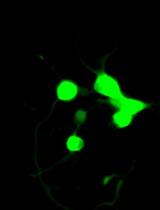

Interleukin-22 (IL-22) has been demonstrated as a critical regulator of epithelial homeostasis and repair; it showed an anti-inflammatory effect against ulcerative colitis. Local microinjection of IL-22 cDNA vector has been shown to be effective in treating ulcerative colitis in mouse models. However, microinjection comes with multiple technical challenges for routine colon-targeted drug delivery. In contrast, oral administration can get around these challenges and provide comparable efficacy. We showed in previous studies that oral administration of new lipid nanoparticles (nLNP)-encapsulated IL-22 mRNA targets the colon region and efficiently ameliorates colitis. This protocol describes the details of preparing and characterizing the nLNP-encapsulated IL-22 mRNA using three major lipids that mimic the natural ginger-derived nanoparticles. It provides an nLNP platform that can be used to orally deliver other types of nucleic acids to the colon.

Interleukin-22 (IL-22) is an anti-inflammatory cytokine that plays a critical role in promoting wound healing during intestinal inflammation. Its expression is decreased in inflamed ulcerative colitis tissue (De Souza and Fiocchi, 2016). Microinjection of IL-22 cDNA into the colon of colitic mice showed its potential in curing ulcerative colitis. Targeted delivery of IL-22 cDNA ameliorated local intestinal inflammation through induction of mucus production, enhancing STAT3 activation in colonic epithelial cells and promoting restitution of goblet cells. Additionally, inhibition of IL-22 activity suppressed goblet cell restitution during the recovery phase of the mouse model (Sugimoto et al., 2008).

We previously used ginger-derived lipid nanoparticles (GDNPs) for orally delivering CD98 siRNA (Zhang et al., 2017) and 6-shogaol (Yang et al., 2021) to treat ulcerative colitis. These studies suggested that GDNPs could overcome the challenges of oral drug delivery. Further, we found that monogalactosyl-diacylglycerol (MGDG), digalactosyl-diacylglycerol (DGDG), and phosphatidic acid (PA) constitute more than 90% of the total lipids of GDNPs (Zhang et al., 2016; Zhang et al., 2017). In this protocol, we will describe how to use these three lipids at the same ratios found in the GDNPs in the synthesis of new lipid nanoparticles (nLNPs) to encapsulate IL-22 mRNA. The nLNP-encapsulated mRNA showed its therapeutic efficacy in one of our recently published studies (Sung et al., 2022).